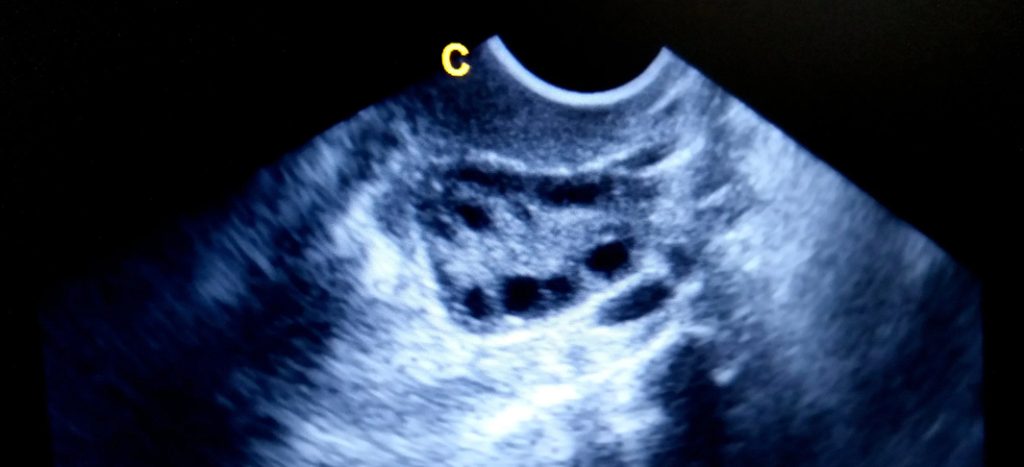

Polycystic Ovary Syndrome (PCOS) is a hormonal condition that affects up to 1 in 10 women. It’s often misunderstood and often missed because the symptoms can be subtle, disconnected, or simply brushed off.

Sometimes PCOS diagnosis is clear. But more often it takes time, consideration, and careful interpretation of results. You don’t need to have cysts on your ovaries to have PCOS, and yet not everyone with cysts has PCOS. What matters more is the broader picture of your cycles, hormones, and symptoms.